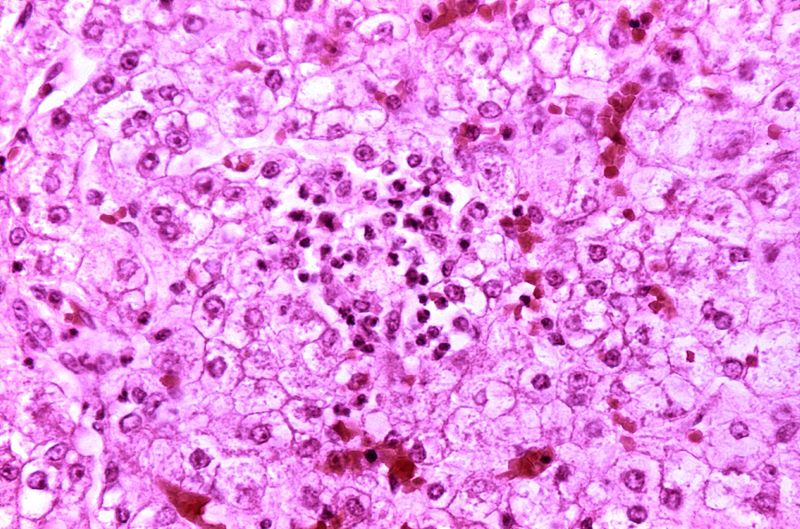

Liver histology shows that the hepatocytes have accumulated brown pigment.

The brown pigment is lipofuscin, a byproduct of the turnover, wear and tear, and peroxidized lipids.

Prussian blue stain differentiates iron from lipofuscin.